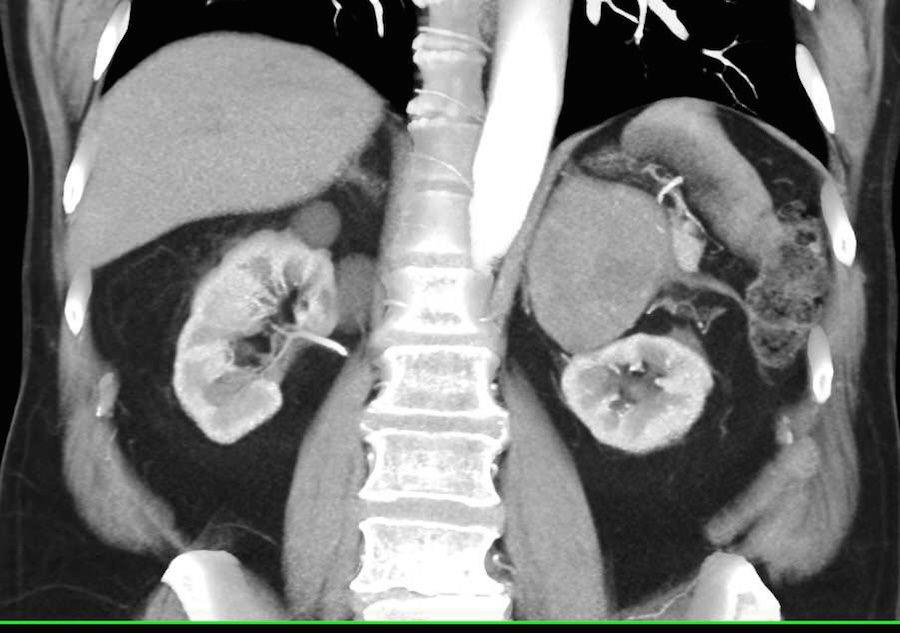

TC DE GLANDULAS SUPRARRENALES.

La hemorragia suprarrenal es una entidad infrecuente que puede ser uní o bilateral.

Cuando es unilateral suele ser clínicamente silente y en la mayor parte de los casos se diagnostica de forma incidental.

Sin embargo, la hemorragia bilateral por lo general desencadena una insuficiencia suprarrenal aguda, a veces dando como resultado el coma o la muerte si la terapia de reemplazo de esteroides no se administra con prontitud.

Las causas de hemorragia suprarrenal se dividen en traumáticas (la mayoría unilaterales y derechas) y espontaneas, agudas y crónicas.